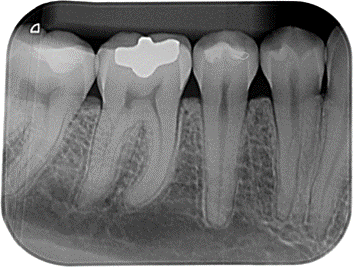

La radiografía periapical digital forma parte de las radiografías intraorales, es una técnica radiográfica que permite al odontólogo obtener imágenes intraorales de alta resolución que sirve para explorar la pieza dentaria de corona a raíz junto con sus estructuras adyacentes.

Este tipo de radiografías se realizan habitualmente en la especialidad de Endodoncia para controlar y verificar el proceso de un tratamiento de conductos, antes, durante y después del tratamiento.

Dentro de la especialidad de periodoncia, en caso de sospecha de alguna posible lesión a nivel de la raíz o alrededor de la pieza dentaria. Se puede llegar a observar si hay pérdida ósea, bolsas periodontales, cálculo entre las piezas dentarias o bajo la encía y quistes periapicales.

También se llega a utilizar para el diagnóstico de caries de esta manera nos ayuda a determinar el grado de afectación si es superficial (de esmalte), o profunda (de dentina), también en caso de caries interproximal.